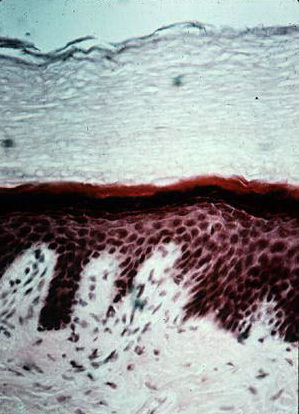

Thick Light Skin = جلد سميك وفاتح